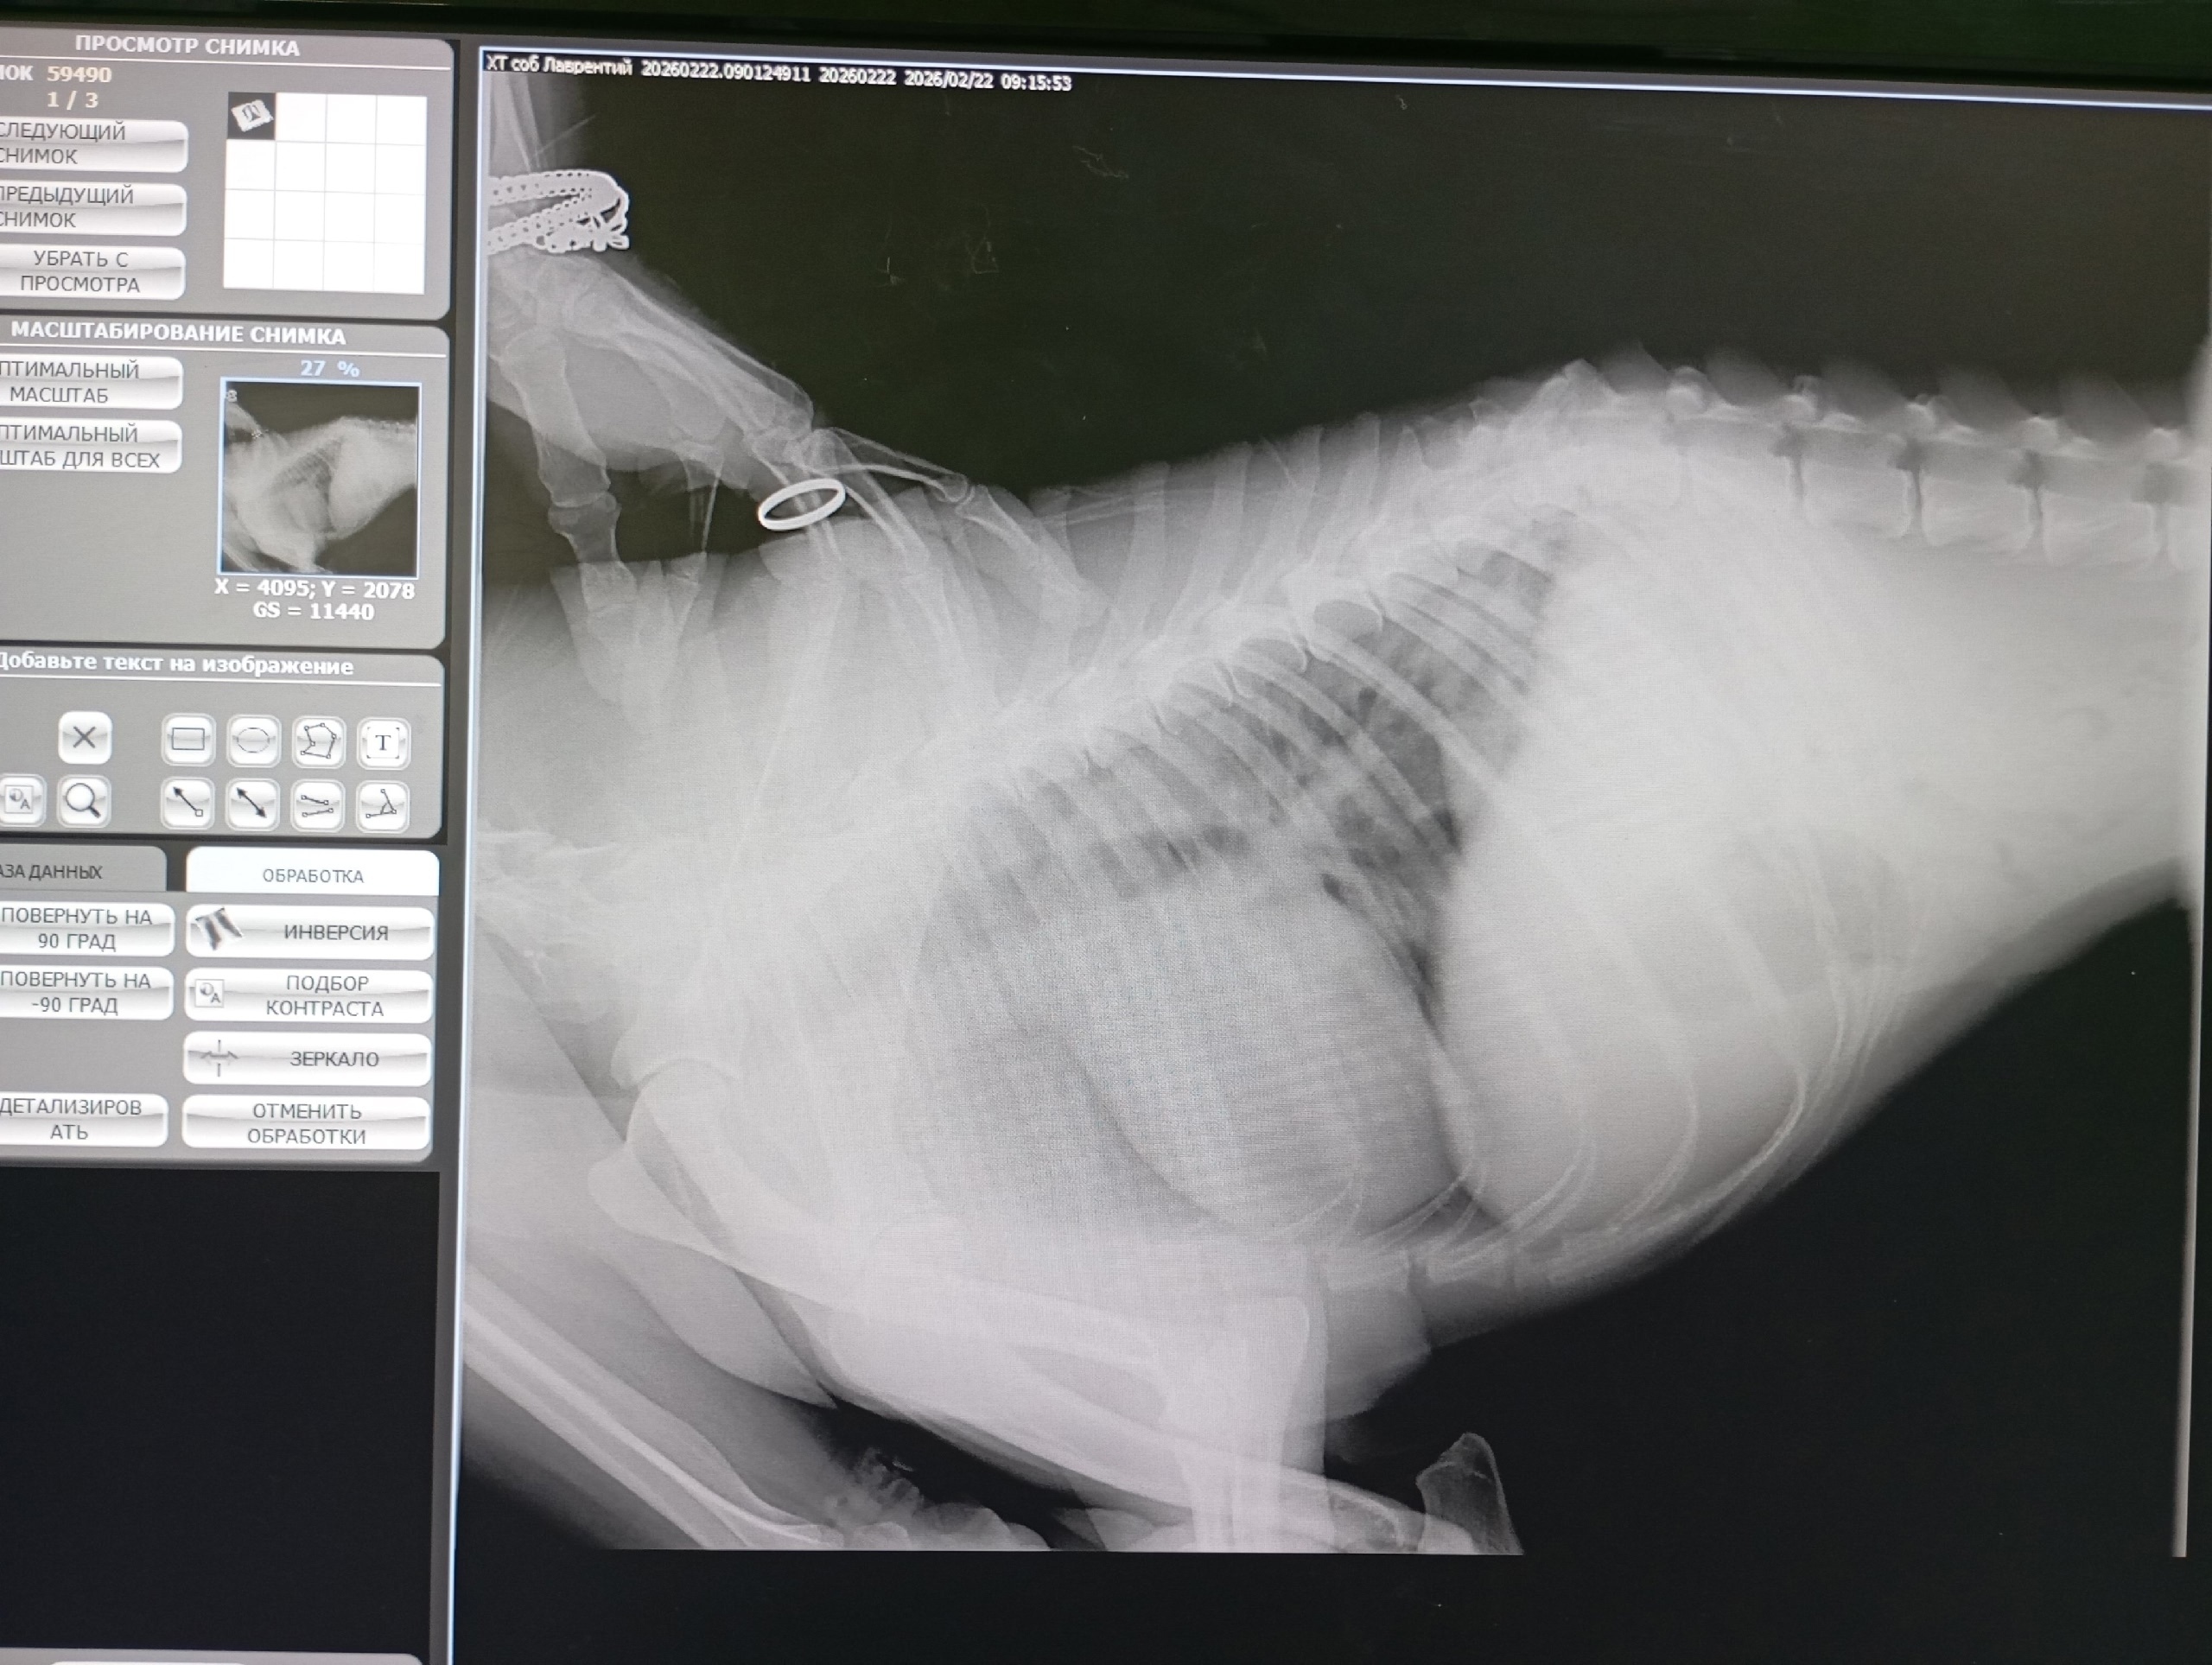

Курск 🐕 Друзья, очень нужны пелёнки, памперсы, средства для обработки от паразитов, а также лежанка для [https://vk.com/wall266026175_115296|бездомыша Лаврентия с переломом позвоночника]! А ещё ему обязательно нужно усиленное питание!

Татьяна Верютина заметила Лавра по кровавым следам на снегу от расчёсанных лап, которые он волочил за собой (см. фото). Татьяна не смогла пройти мимо и приютила тяжело травмированного бедолагу.